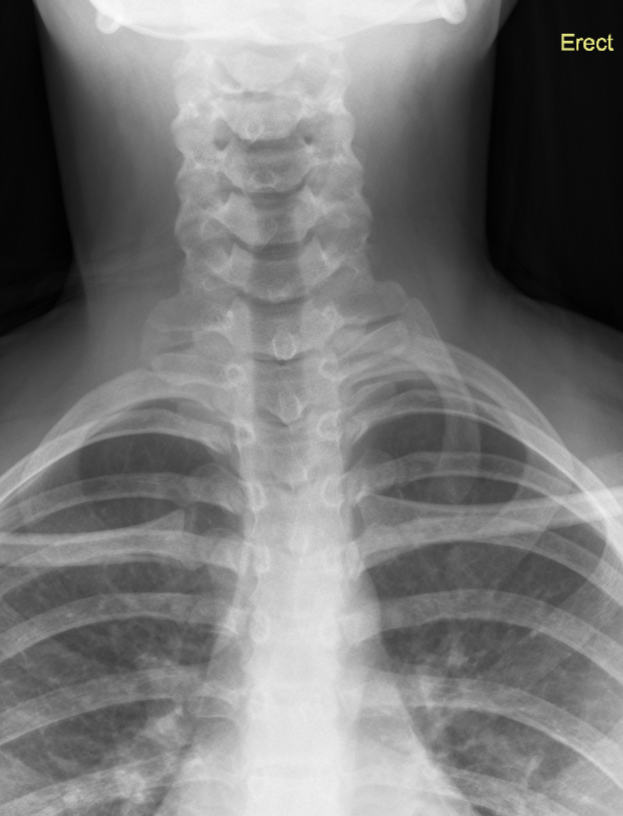

3. Left cervical rib